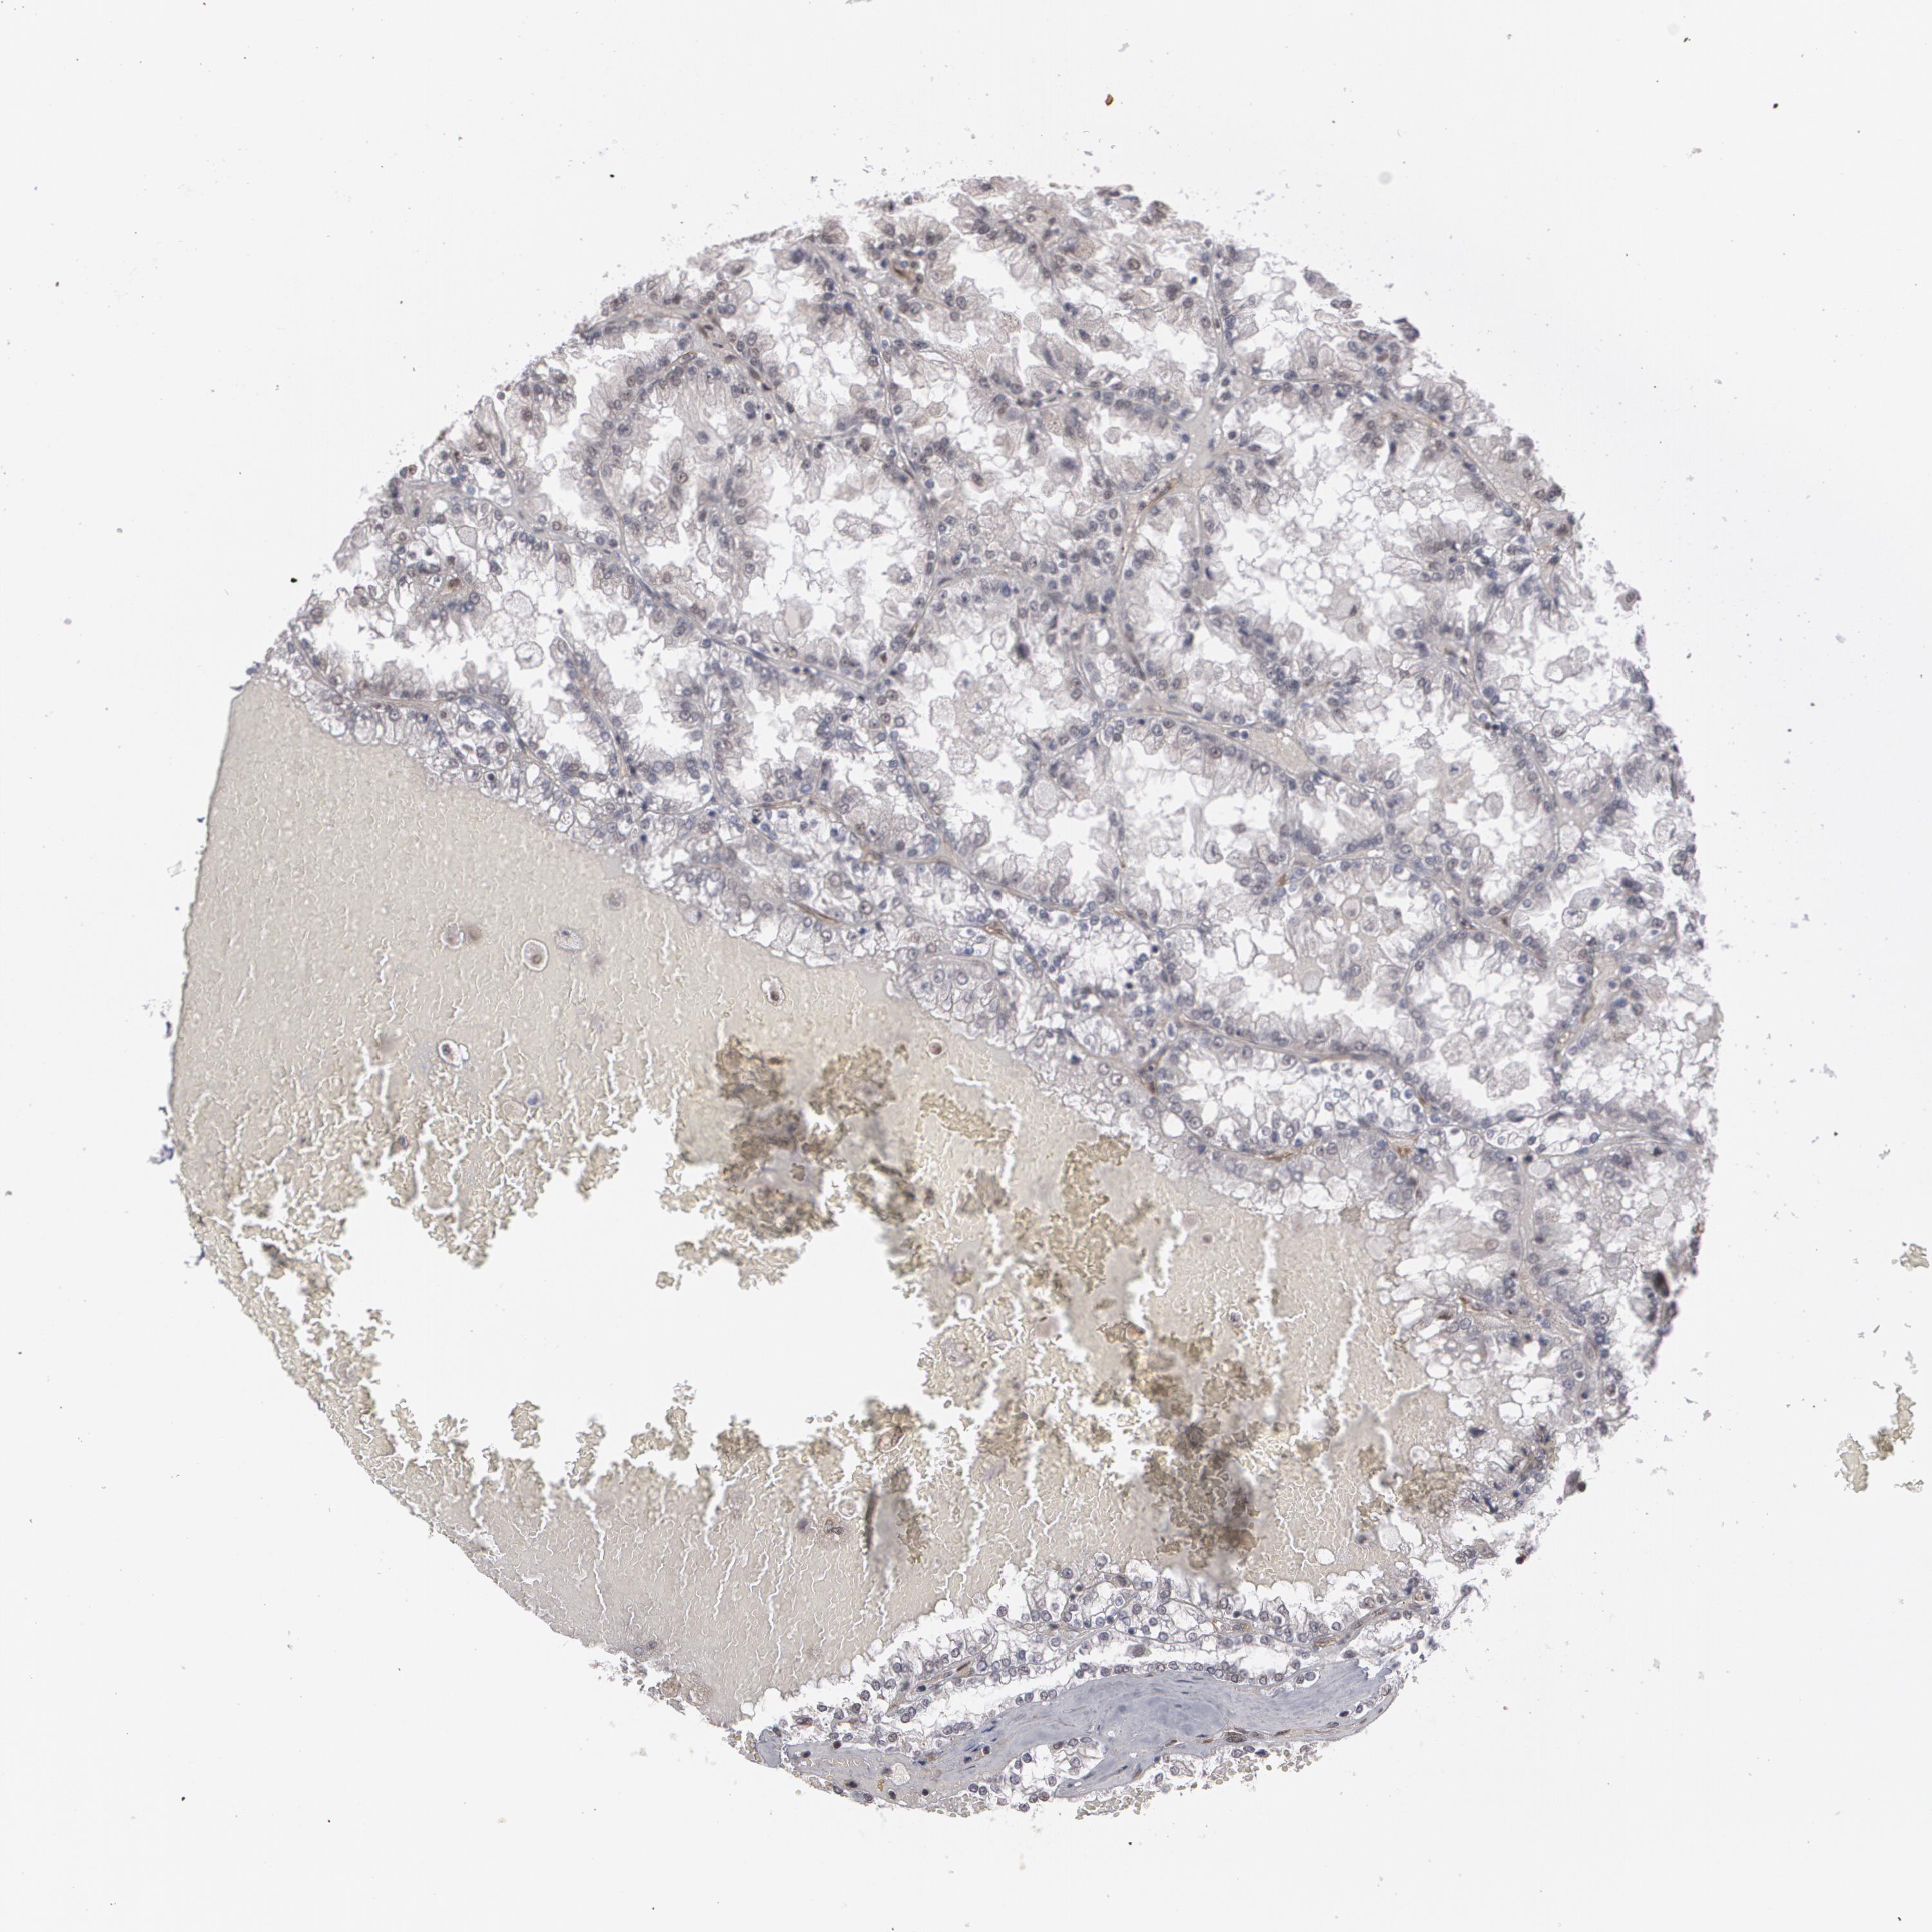

KIDNEY RENAL PAPILLARY CELL CARCINOMA (TCGA) - Interactive survival scatter ploti

The Survival Scatter plot shows the clinical status (i.e. dead or alive) for all individuals in the patient cohort, based on the same data that underlies the corresponding Kaplan-Meier plots. Patients that are alive at last time for follow-up are shown in blue and patients who have died during the study are shown in red.

The x-axis shows the expression levels (FPKM) of the investigated gene in the tumor tissue at the time of diagnosis. The y-axis shows the follow-up time after diagnosis (years). Both axes are complimented with kernel density curves demonstrating the data density over the axes. The top density plot shows the expression levels (FPKM) distribution among dead (red) and alive patients (blue). The right density plot shows the data density of the survived years of dead patients with high and low expression levels respectively, stratified using the cutoff indicated by the vertical dashed line through the Survival Scatter plot. This cutoff is automatically defined based on the FPKM cutoff that minimizes the p-score. The cutoff can be changed by dragging the vertical line or by entering a cutoff value in the square labeled "Current cut-off".

Under the Survival Scatter plot the p-score landscape (black curve; left axis) is shown together with dead median separation (red curve; right axis). Dead median separation is the difference in median mRNA expression between patients who have died with high and low expression, respectively. It is calculated as follows: median FPKM expression of dead patients with high expression - median FPKM expression of dead patients with low expression. This is intended to aid the user in visually exploring custom cutoffs and the associated p-scores and dead median separation.

Individual patient data is displayed and can be filtered by clicking on one or more of the category buttons on the top of the page. Categories describing expression level and patient information include: high, low, alive, dead, female, male and tumor stages. The scale of the x-axis can be toggled between linear and log-scale by clicking on the "x log" button. Mouse-over function shows TCGA ID, patient information and mRNA expression (FPKM) for each patient.

& Survival analysisi

Kaplan-Meier plots summarize results from analysis of correlation between mRNA expression level and patient survival. Patients were divided based on level of expression into one of the two groups "low" (under cut off) or "high" (over cut off). X-axis shows time for survival (years) and y-axis shows the probability of survival, where 1.0 corresponds to 100 percent.

ZNF75A is not prognostic in Kidney Renal Papillary Cell Carcinoma (TCGA)

Best expression cut offi

Based on the FPKM value of each gene, patients were classified into two groups and association between prognosis (survival) and gene expression (FPKM) was examined. The best expression cut-off refers the FPKM value that yields maximal difference with regard to survival between the two groups at the lowest log-rank P-value. Best expression cut-off was selected based on survival analysis .

When clicking on this number, the vertical dashed line indicating cut-off, the interactive survival plot, and the Kaplan-Meier curve will be adjusted to show results based on the best expression cut-off.